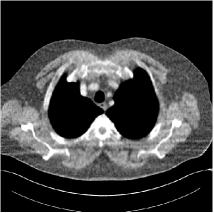

Refer to caption

Fig. 4: FBP images of test examples.